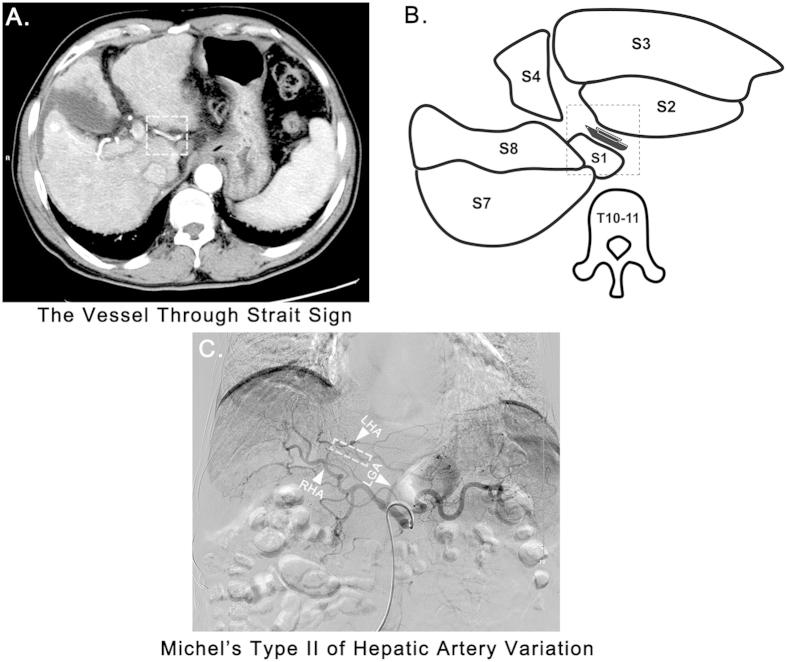

The "Vessel through Strait" Sign is a Signature Radiological Sign for the Diagnosis of Left Hepatic Artery Variation.

An aberrant artery (AA) can frequently be observed coursing through the fissure for the ligamentum venosum (FLV) which was termed the "vessel through strait" sign (VTSS) by us. Fundamental data including the incidence, anatomical composition and clinical significance of VTSS and the AAs composing VTSS are still lacking. We sought to give a systematic demonstration on this issue in the present study. VTSS was respectively analyzed in 2,275 patients and was observed in 357 of them. Interestingly, 319 (89.4%) out of the 357 patients exhibiting VTSS were proved to have left hepatic artery variation (LHAV) (247 with replaced left hepatic artery, 64 with accessory left hepatic artery and 8 with variant common hepatic artery). We therefore hypothesized that VTSS could be a sign that strongly associated with LHAV and could be used for its diagnosis. In the following validating analysis, VTSS gained a sensitivity of 96.3% and a specificity of 98.3% for the diagnosis of LHAV in another bicenter cohort consisted of 1,329 patients. In conclusion, VTSS is a signature radiological sign of LHAV which could be used as an easy and specific method for the diagnosis of LHAV.